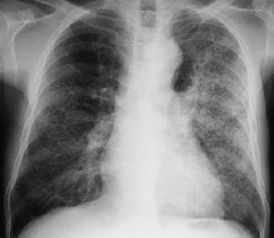

(一)胸部X線檢查:最常見表現(xiàn)為支氣管肺炎型改變,通常無助于肺炎病原的確定,但某些特征對診斷可有所提示,如肺葉實變、空洞形成或較大量胸腔積液多見于細菌性肺炎。

葡萄球菌肺炎可引起明顯的肺組織壞死、肺氣囊、肺膿腫和膿胸。革蘭陰性桿菌肺炎常呈下葉支氣管肺炎型,易形成多發(fā)性小膿腔。

對肺炎診斷有重要價值,炎性浸潤陰影的部位、范圍,有無空洞、胸腔積液等與病原菌有關。, 不同病原菌的肺炎X線表現(xiàn), , , X線表現(xiàn), 病原菌, , , 葉或段低密度片狀浸潤, 肺炎鏈球菌,流感嗜血桿菌,克雷白肺炎桿菌,大腸桿菌,軍團菌, , , 均勻性浸潤(斑片或條索狀陰影), 肺炎支原體、病毒、厭氧和非厭氧菌混合感染、軍團菌屬, , , 彌漫性均勻性浸潤或結(jié)節(jié)狀陰影, 軍團菌屬、病毒、卡氏肺囊蟲病,分支桿菌屬,曲霉菌,念珠菌屬,血行播散性感染, , , 空洞性浸潤, 金黃色葡萄球菌,革蘭陰性菌,厭氧菌,結(jié)核桿菌,曲霉菌, , , (二)細菌學檢查:痰或胸水涂片檢查,培養(yǎng)致病菌及抗生素敏感試驗.連續(xù)2、3次為同一細菌生長,致病菌的可能性大,僅一次陽性或多次為不同細菌生長,則可靠性差。

常見白細胞增多,但血清LDH常正常。胸片示肺以葉或節(jié)段性分布或網(wǎng)狀結(jié)締狀浸潤,金葡菌感染可形成空洞。

此外,心力衰竭、有害氣體的吸入、長期臥床的肺水腫、肺淤血、以及腦外傷等都有利于細菌的感染和生長繁殖,導致肺炎。 肺炎的診斷: 血液檢查時末梢白細胞計數(shù)可達每立方毫米20000—30000,中性粒細胞增至80%以上,在實變期可見大片均勻致密的陰影,典型的分布限于肺段或肺葉,但大多數(shù)為片狀。